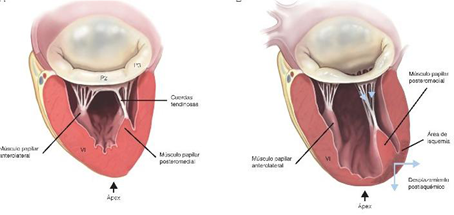

Las cuerdas tendinosas se originan en los músculos papilares y se insertan en el borde libre de los velos; las cuerdas secundarias en la cara ventricular del cuerpo de los velos y las terciarias en la cara ventricular de la base de ambos velos.(Figura 4)

Los músculos papilares son 2, el anterolateral, que recibe doble irrigación (de las arterias circunfleja y descendente anterior, mientras el músculo póstero medial es irrigado por una sola arteria (la coronaria derecha o la circunfleja).

Finalmente el tamaño y la forma del ventrículo izquierdo impactan en la función de la válvula mitral(9).(Figura 6) Cuando el ventrículo se dilata se torna más esférico, los músculos papilares se desplazan apicalmente, limitando así el cierre correcto de la válvula(10).